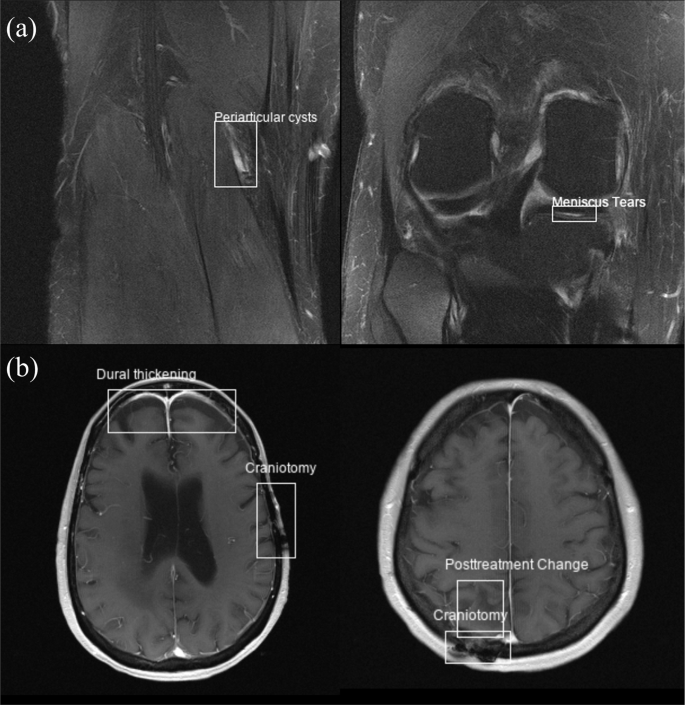

The bounding box information can be used to plot overlaid bounding boxes on images, as shown in Fig. 1. The clinical labels, together with the bounding box coordinates, can also be converted to other formats (e.g., YOLO format20) in order to configure a classification or object detection problem. The open-source repository also contains an example Jupyter Notebook (‘ExampleScripts/example.ipynb’) of how to read the annotations and plot images with bounding boxes in Python.

Example annotations (labels and bounding boxes) from the fastMRI+ dataset shown superimposed on both knee (a) and brain (b) reconstructed images from the fastMRI dataset.